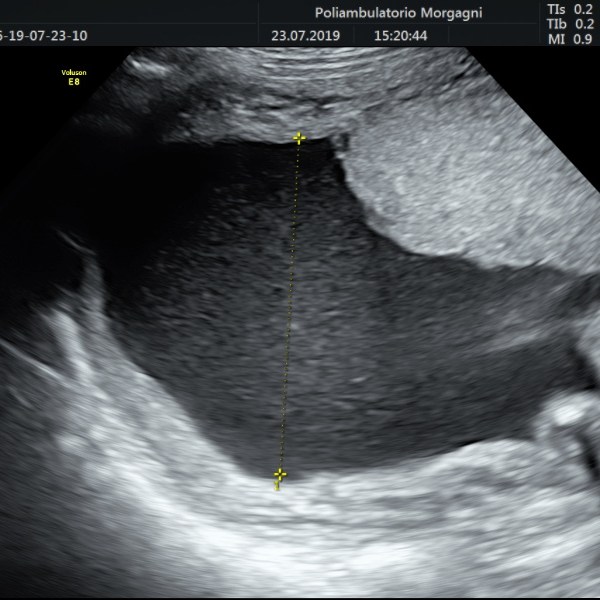

Il mese si conclude con l’ecografia di accrescimento da non eseguire troppo precocemente per ridurre il lasso di tempo fino al momento del parto.

Oltre la valutazione della biometria fetale, è importante controllare il benessere fetale con flussimetria a livello del cordone ombelicale e la quantità di liquido amniotico, vera cartina di tornasole del benessere fetale.